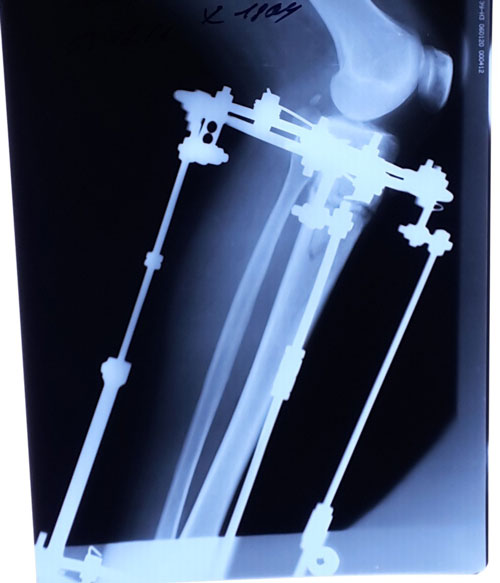

Рентген в 62 дня.

Сращение идёт отлично для этого срока и возраста пациентки.